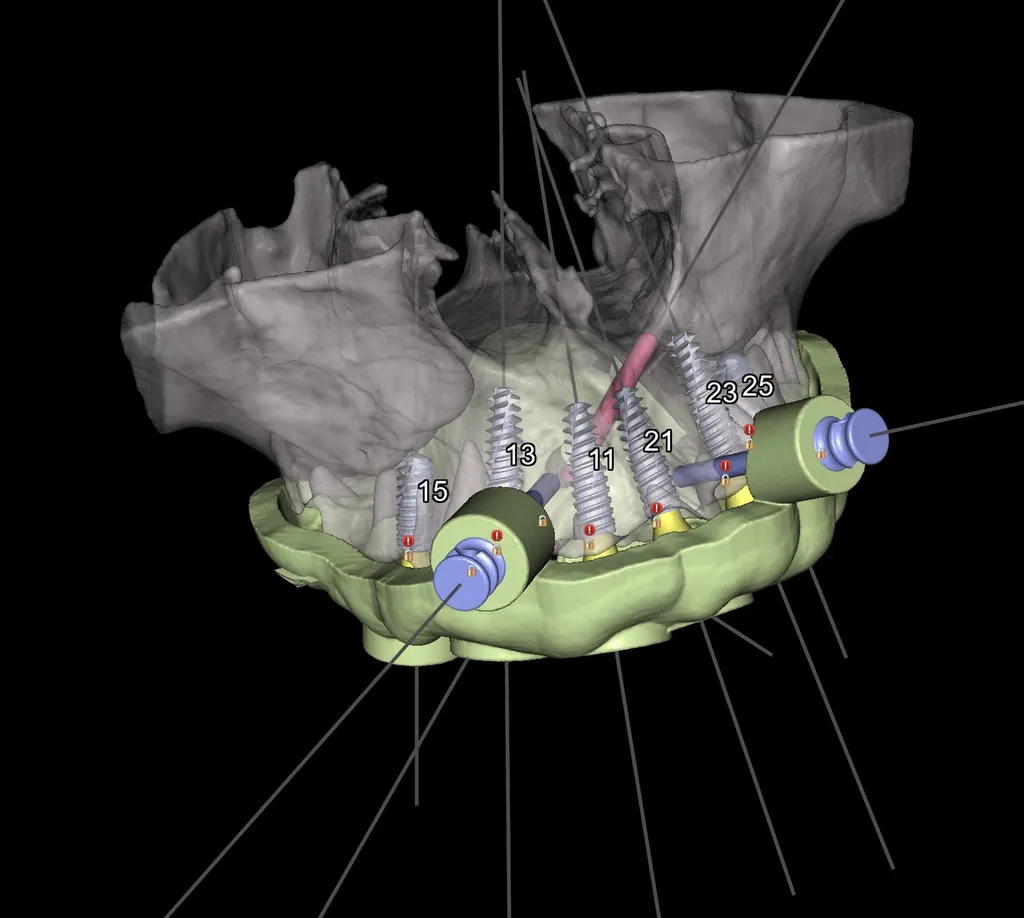

Consultation et Diagnostic 3D : Un examen clinique approfondi et un scanner 3D (Cone Beam) sont réalisés pour évaluer la quantité et la qualité de votre os alvéolaire, planifier la pose des implants avec une extrême précision et établir un devis personnalisé.

Précision et Sécurité Maximale avec la Chirurgie Guidée

Scanner 3D (Cone Beam) pour évaluer la densité et le volume osseux

Simulation virtuelle de la pose des 6 implants grâce à un logiciel de planification

Fabrication d'un guide chirurgical sur mesure pour une pose mini-invasive

Via le guide chirurgical, pose des 6 implants en titane avec une précision millimétrique

Les implants postérieurs sont parfois inclinés pour optimiser l'ancrage sans greffe osseuse